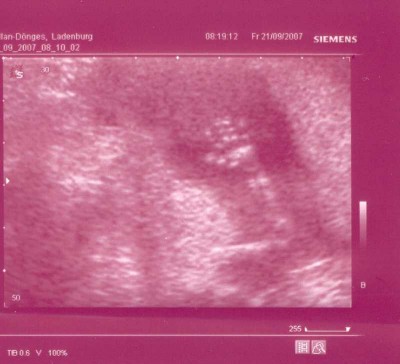

Naja endlich kam dann der US und zum Glück mit unserem Knödel ist alles OK ! Schön gewachsen auf 8,87cm und ganz eingekuschelt in meiner GM lag er/sie, da meinte meine FÄ dass Sie das Baby in dieser Lage leider nicht messen kann und SCHWUPS hat sich unser Knödel ganz genüsslich gestreckt und wir konnten schön messen.

Knödel  SSW 14+6.JPG

Ach so unser Knödel wollte euch auch mal winken

Knödelhand  SSW 14+6.JPG